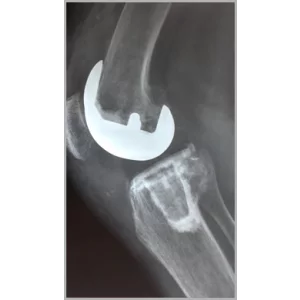

Right Total Hip Replacement And Right Total Knee Replacement In Single Stage Only